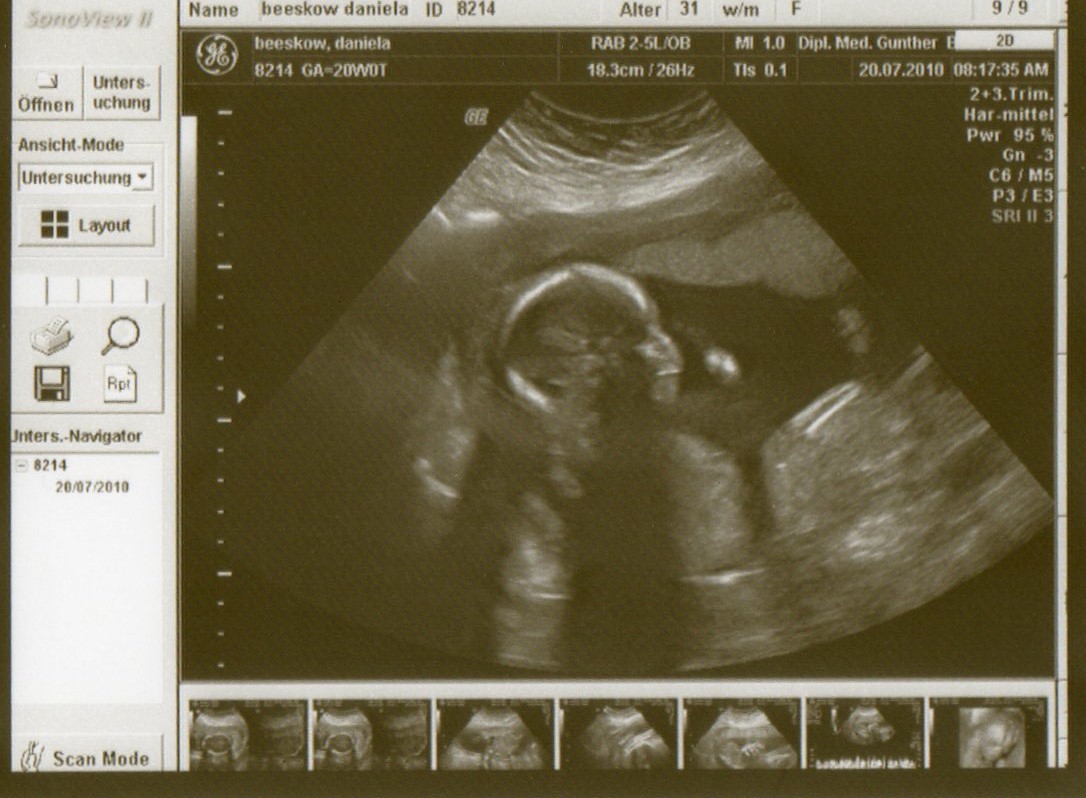

Hab morgen schon Halbzeit. Wahnsinn, wo ist nur die Zeit geblieben. :ohnmacht: War gestern zum 2. großen Schall. Mit Zwergl ist alles in bester Ordnung, hat auch fleißig geturnt und sich am Kopf gekratzt und immer wenn der Doc versucht hat ein anständiges 3D Bild vom Gesicht zu bekommen die Hände vor das Gesicht genommen bzw. das Gesicht gegen den Schallkopf gedrückt. *rotfl* Hatten uns eigentlich selbst um einen Termin bemüht zwecks 3D und 4D Aufnahmen. Aber nun gab es gestern vom Doc doch noch die Überweisung zur Feindiagnostik, obwohl er selbst ein tolles Gerät hat. Da haben wir nun am 5.8. Termin und hoffen, das die Vermutung von uns und dem Gyn bestätigt wird.

Denn so wie es ausschaut, erwarten wir unsere 3. Prinzessin. Nun hoffen wir mal, das bei der FD das ganze bestätigt wird und sich da nicht doch noch ein Zipfel versteckt hat.

Hier das US Bild von gestern

Baby5.jpg